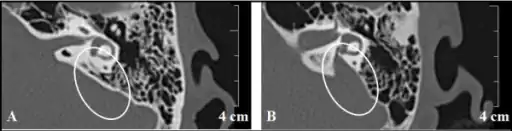

a)Vestibular aqueduct is not identified in control subject b) enlarged vestibular aqueduct is identified in a person with EVA

Enlarged vestibular aqueducts are commonly picked up after newborn hearing screen when a child is identified as having a hearing loss. The hearing loss is commonly mixed and can be of any degree when first identified. The conductive component is due to a third window effect caused by the widened vestibular aqueduct. During an audiologic assessment, an air-bone gap in the low frequencies can occur due to the enlarged vestibular aqueduct acting as a third mobile window. Hearing loss in the contralateral ear to the enlarged vestibular aqueduct can also occur due to the chemical composition on both sides.[5] Torticollis has also been found to be an indicator of an enlarged vestibular aqueduct in children.[6] Identification of the enlarged vestibular aqueduct in a child is usually by MRI scan which identifies the fluid within the endolymphatic duct and sac. CT scan may be needed to see the vestibular aqueduct clearly. In adults CT scan may be the first investigation. In order to diagnose the cause of the enlarged vestibular aqueduct the physician will need a detailed family history, full examination to include vestibular examination and, if a bilateral finding, molecular genetic testing as appropriate. With unilateral enlarged vestibular aqueducts molecular genetic testing is currently not recommended.